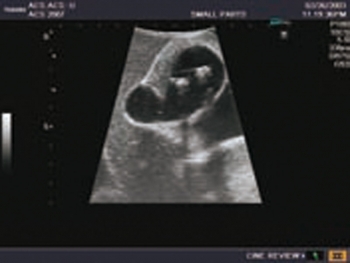

Ultraschall-Modell für die intraoperative abdominelle und laparoskopische Sonografie Eigenschaften

- Ein künstliches Modell für die Ausbildung eines Anfängers nach Demonstration durch einen Fachmann.

- Die genaue Darstellung der Anatomie der Leber und Gallenwege, des Pankreas und des übrigen Abdomens entspricht den höchsten Anforderungen an eine exzellente Ausbildung: offene intraoperative Sonografie von Leber, Gallengängen und Pankreas; die laparoskopische Untersuchung des Gallensystems zur Prüfung auf eine Steinbildung und Beurteilung auf Leber- und Pankreasläsionen etc.

- Die weichen Materialien des Modells ermöglichen eine realistische Sondenführung. Verschiedene Läsionssimulationen wie Gallensteine und -zysten, solide Tumore (echoarm, echoreich, entsprechend der Echostruktur des simulierten Objekts) in Leber, Pankreas und Nieren.